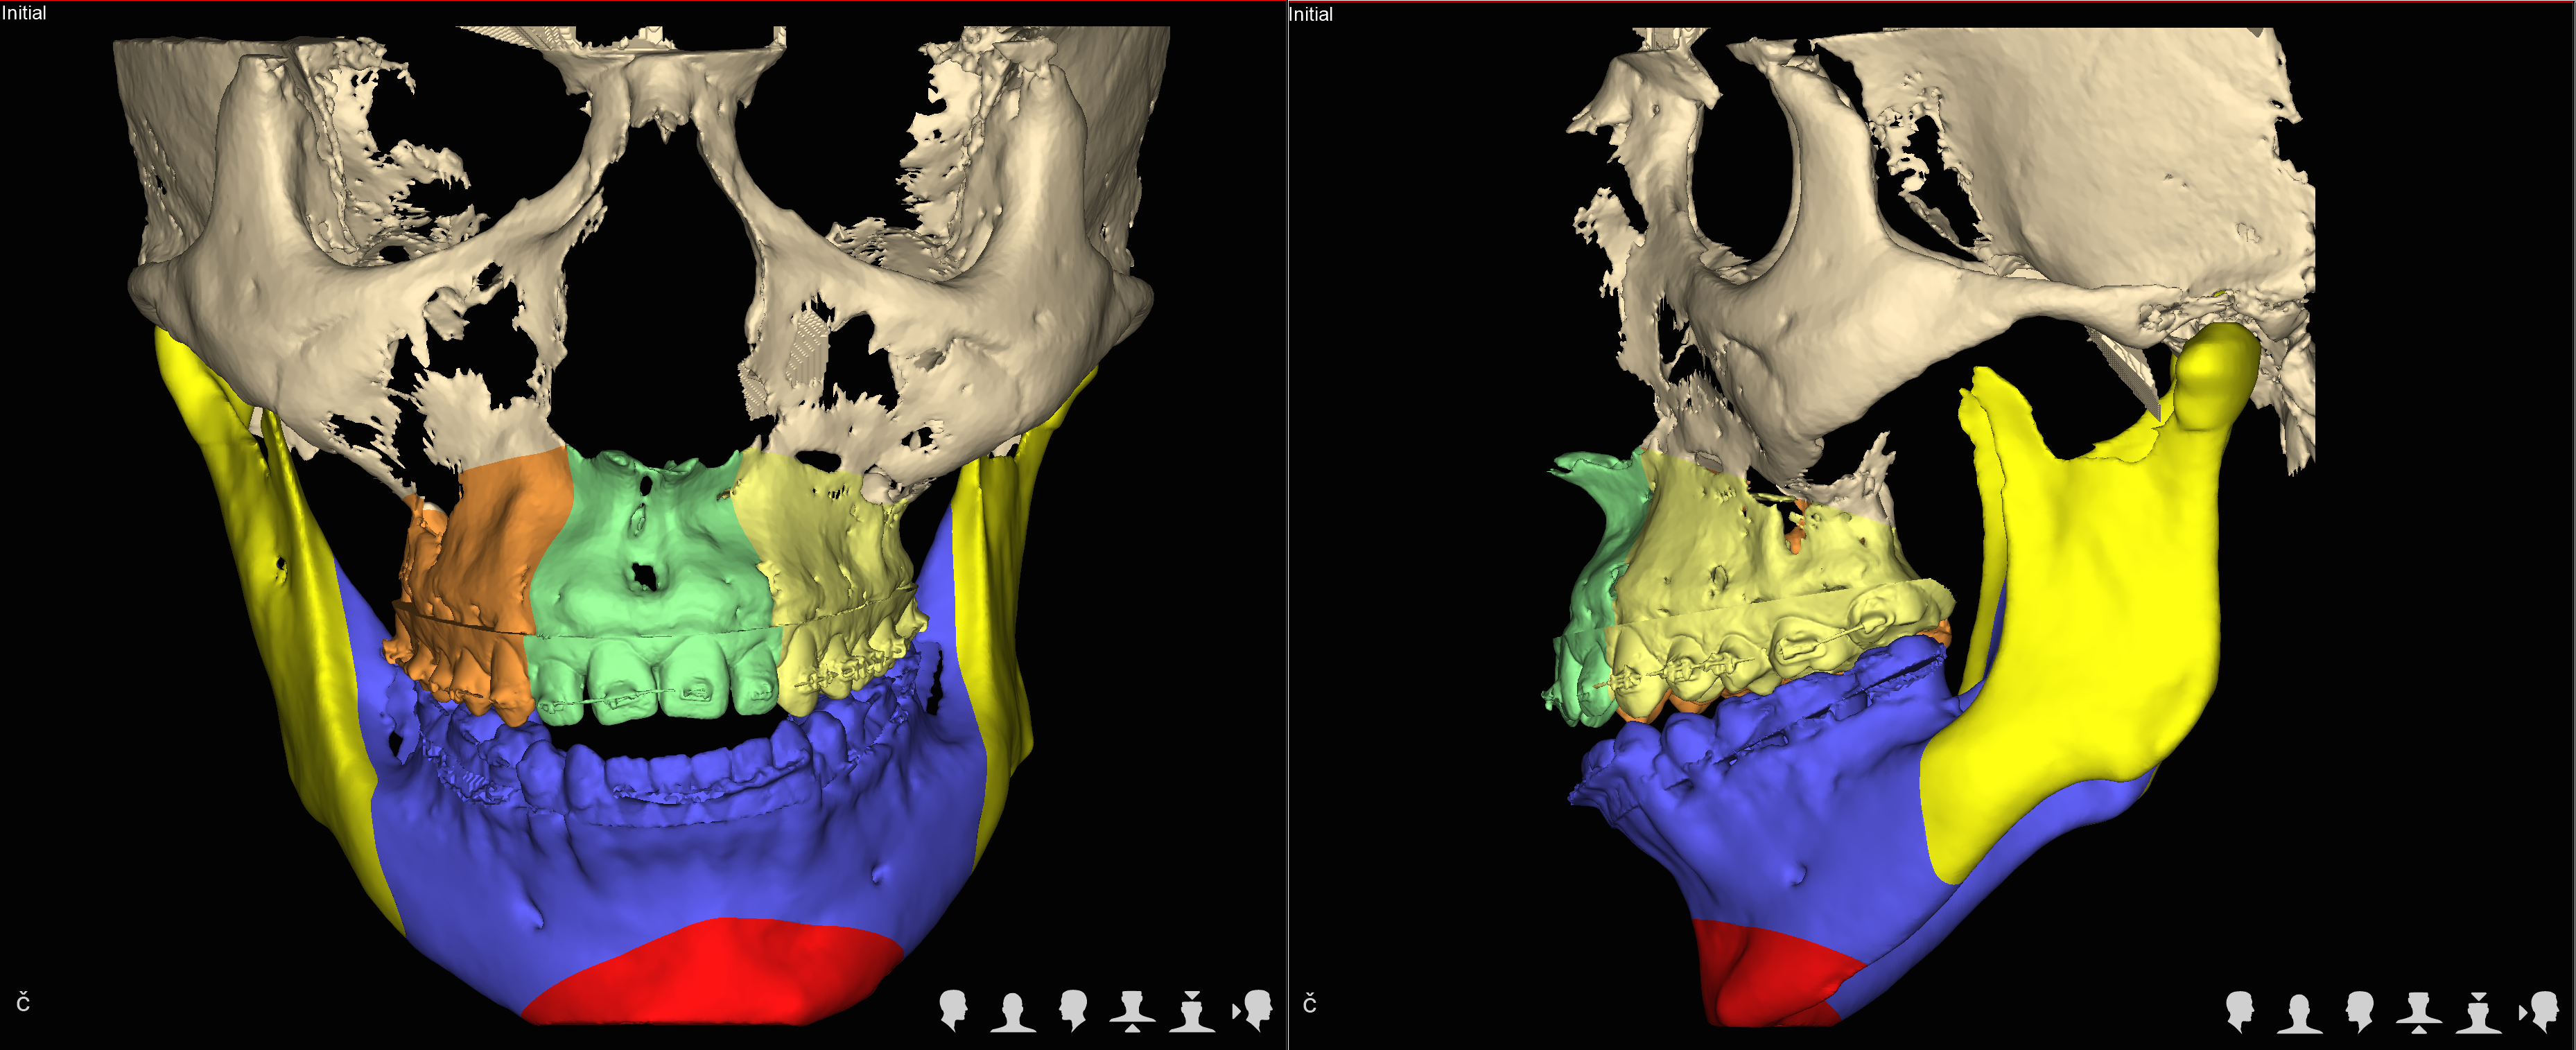

Trójwymiarowe planowanie leczenia wad zgryzu

Nie wyobrażamy sobie planowania operacji wady zgyzu inaczej niż w środowisku 3D.

Jedną z najistotniejszych części leczenia interdyscyplinarnego pacjentów z wadami szkieletowymi jest właściwe zaplanowanie całego procesu leczenia zarówno pod względem przesunięć zębów jak też zmian w układzie kostnym.

Szkielet czaszki twarzowej jest bryłą przestrzenną i rozpatrywanie jego nieprawidłowości w układzie trójwymiarowym pozwala na prawidłowe ich zdiagnozowanie a tym samym na optymalne zaplanowanie przesunięć kostnych, uzyskanie właściwych proporcji twarzy.

W naszym Centrum wykorzystujemy koncepceję FAB (FaceAirwayBite) opracowaną przez Williama Arnetta – światowej sławy chirurga zajmującego się leczeniem wad zgryzu.

Następnie rekomendujemy lub wdrażamy postępowanie ortodontyczne. Po jego zakończeniu przystępujemy ponownie do analiz wszystkich parametrów w obrębie twarzy i przygotowujemy plan leczenia chirurgicznego obejmjący przesunięcia kostne z zakresie układu szkieletowego z uwględnieniem koncepcji FAB.

Docelowo efektem jest wydruk szablonów chirurgicznych na drukarce 3D.

W trakcie planowania powstają rownież symulacje efektów leczenia (symulacje a więc nie gwarantowany efekt), które są przedstawiane pacjentowi przed wykonaniem zabiegu.